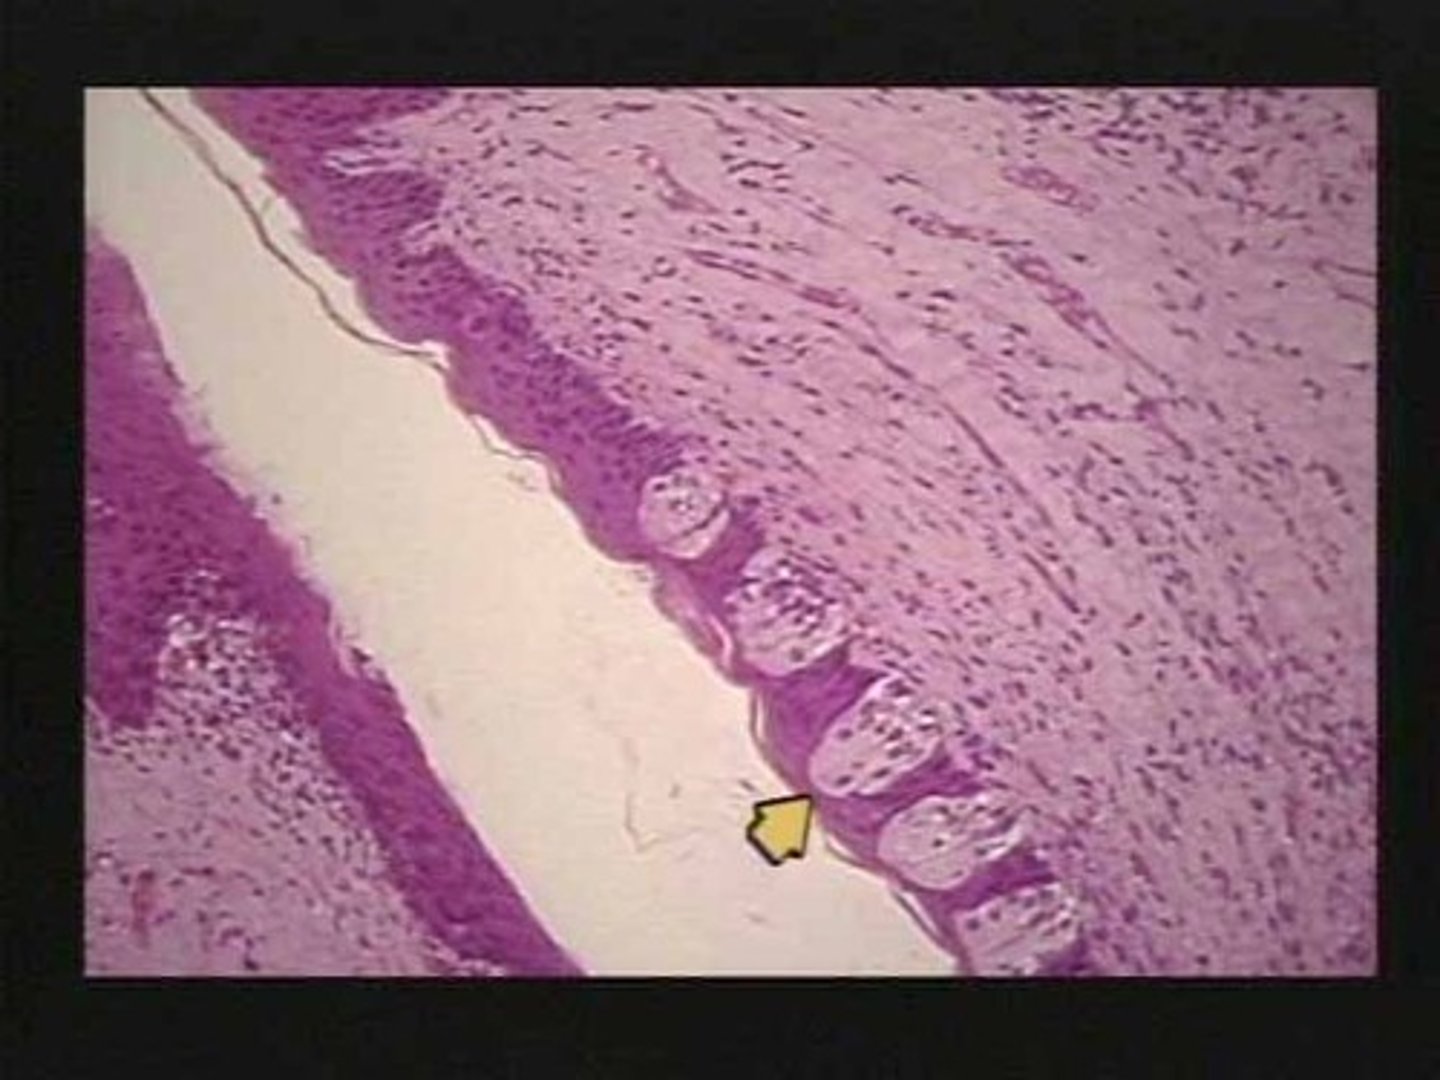

Salivary gland

Mucous cell

Serous cell